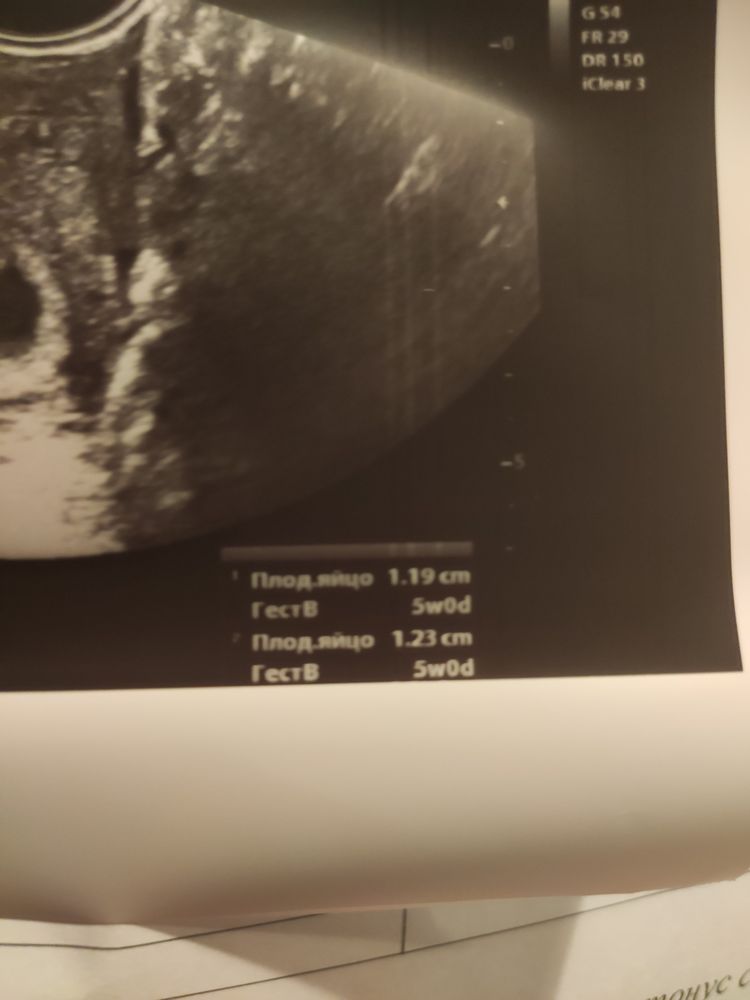

Алёна Тарасенко 4 года Help me Приветики. Девочки, здесь же норм все для 5 АК недель? Посмотрите еще 20 записей на эту тему Отменить Ответить Нина Вижу только надпись про ПЯ. 1,23 см? 14.07.2021 Ответить Алёна Тарасенко Нина, почему 2 показателя? 14.07.2021 Ответить Нина Алёна Тарасенко, ну оно же не идеально круглое. Вот и померили два размера. Среднее между ними считается размером ПЯ. 14.07.2021 Ответить Алёна Тарасенко Нина, спасибо 14.07.2021 Ответить Help me Чаты Беременных Выберите чат: Январята-2026 Февралята-2026 Мартята-2026 Апрелята-2026 Майчата-2026 Июнята-2026 Июлята-2026 Августята-2026